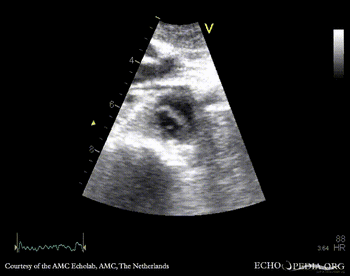

Subcostal view: mobile structure (thrombus) in abdominal aorta